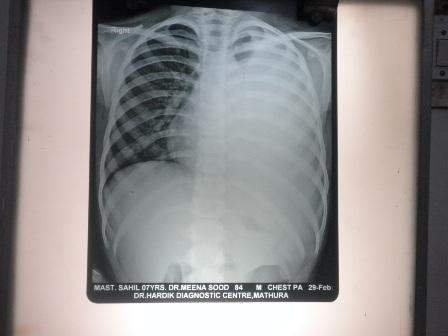

sahil aged 7 years

sahil after tretment with 2 month

sahil before treatment